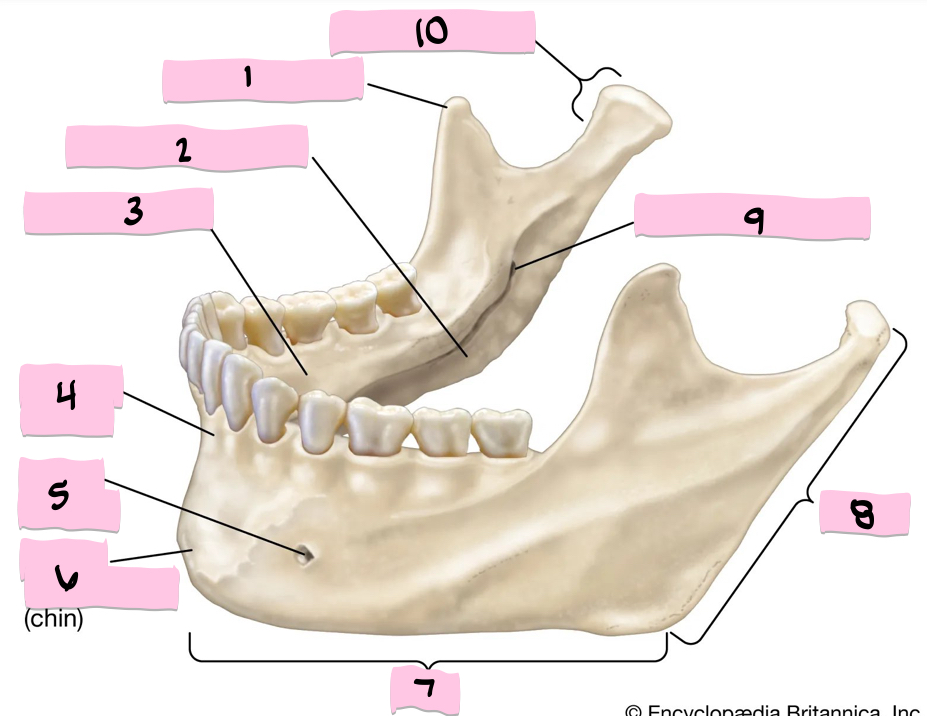

What is 1 pointing to?

Coronoid process

What is 2 pointing to?

Submandibular fossa

What is 3 pointing to?

Sublingual fossa

What is 4 pointing to?

Alveolar process

What is 5 pointing to?

Mental foramen

What is 6 pointing to?

Mental protuberance

What is 7 pointing to?

Body

What is 8 pointing to?

Ramus

What is 9 pointing to?

Mandibular foramen

What is 10 pointing to?

Condylar process